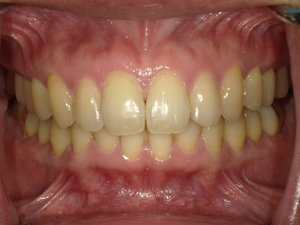

すきっぱ(空隙歯列)CASE4 2023.06.06 40代女性非抜歯BEFORE→AFTER〇ご相談内容:歯と歯の間があいている、下の歯のがたつき〇矯正の種類:マウスピース型矯正「インビザラインGO」〇治療期間:17週間〇治療費用:44万円(税込) < すきっぱ(空隙歯列)CASE5すきっ歯(空隙歯列弓)CASE3 > ブログ記事一覧をみる